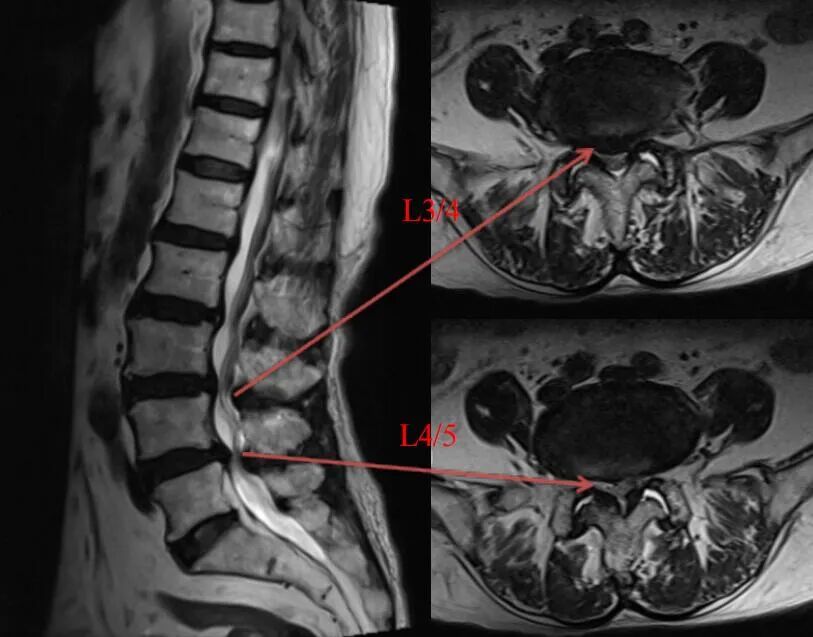

术前

术前MRI(王奶奶)

脊柱外科丰荣杰主任医师团队检查后发现老人存在严重的腰椎管狭窄,伴有腰椎不稳、退变性侧弯等,神经根及马尾神经长期受到卡压,若长此以往,很容易出现神经损伤、下肢瘫痪、大小便功能障碍,导致长期卧床,从而出现各种并发症,最终会危及生命。